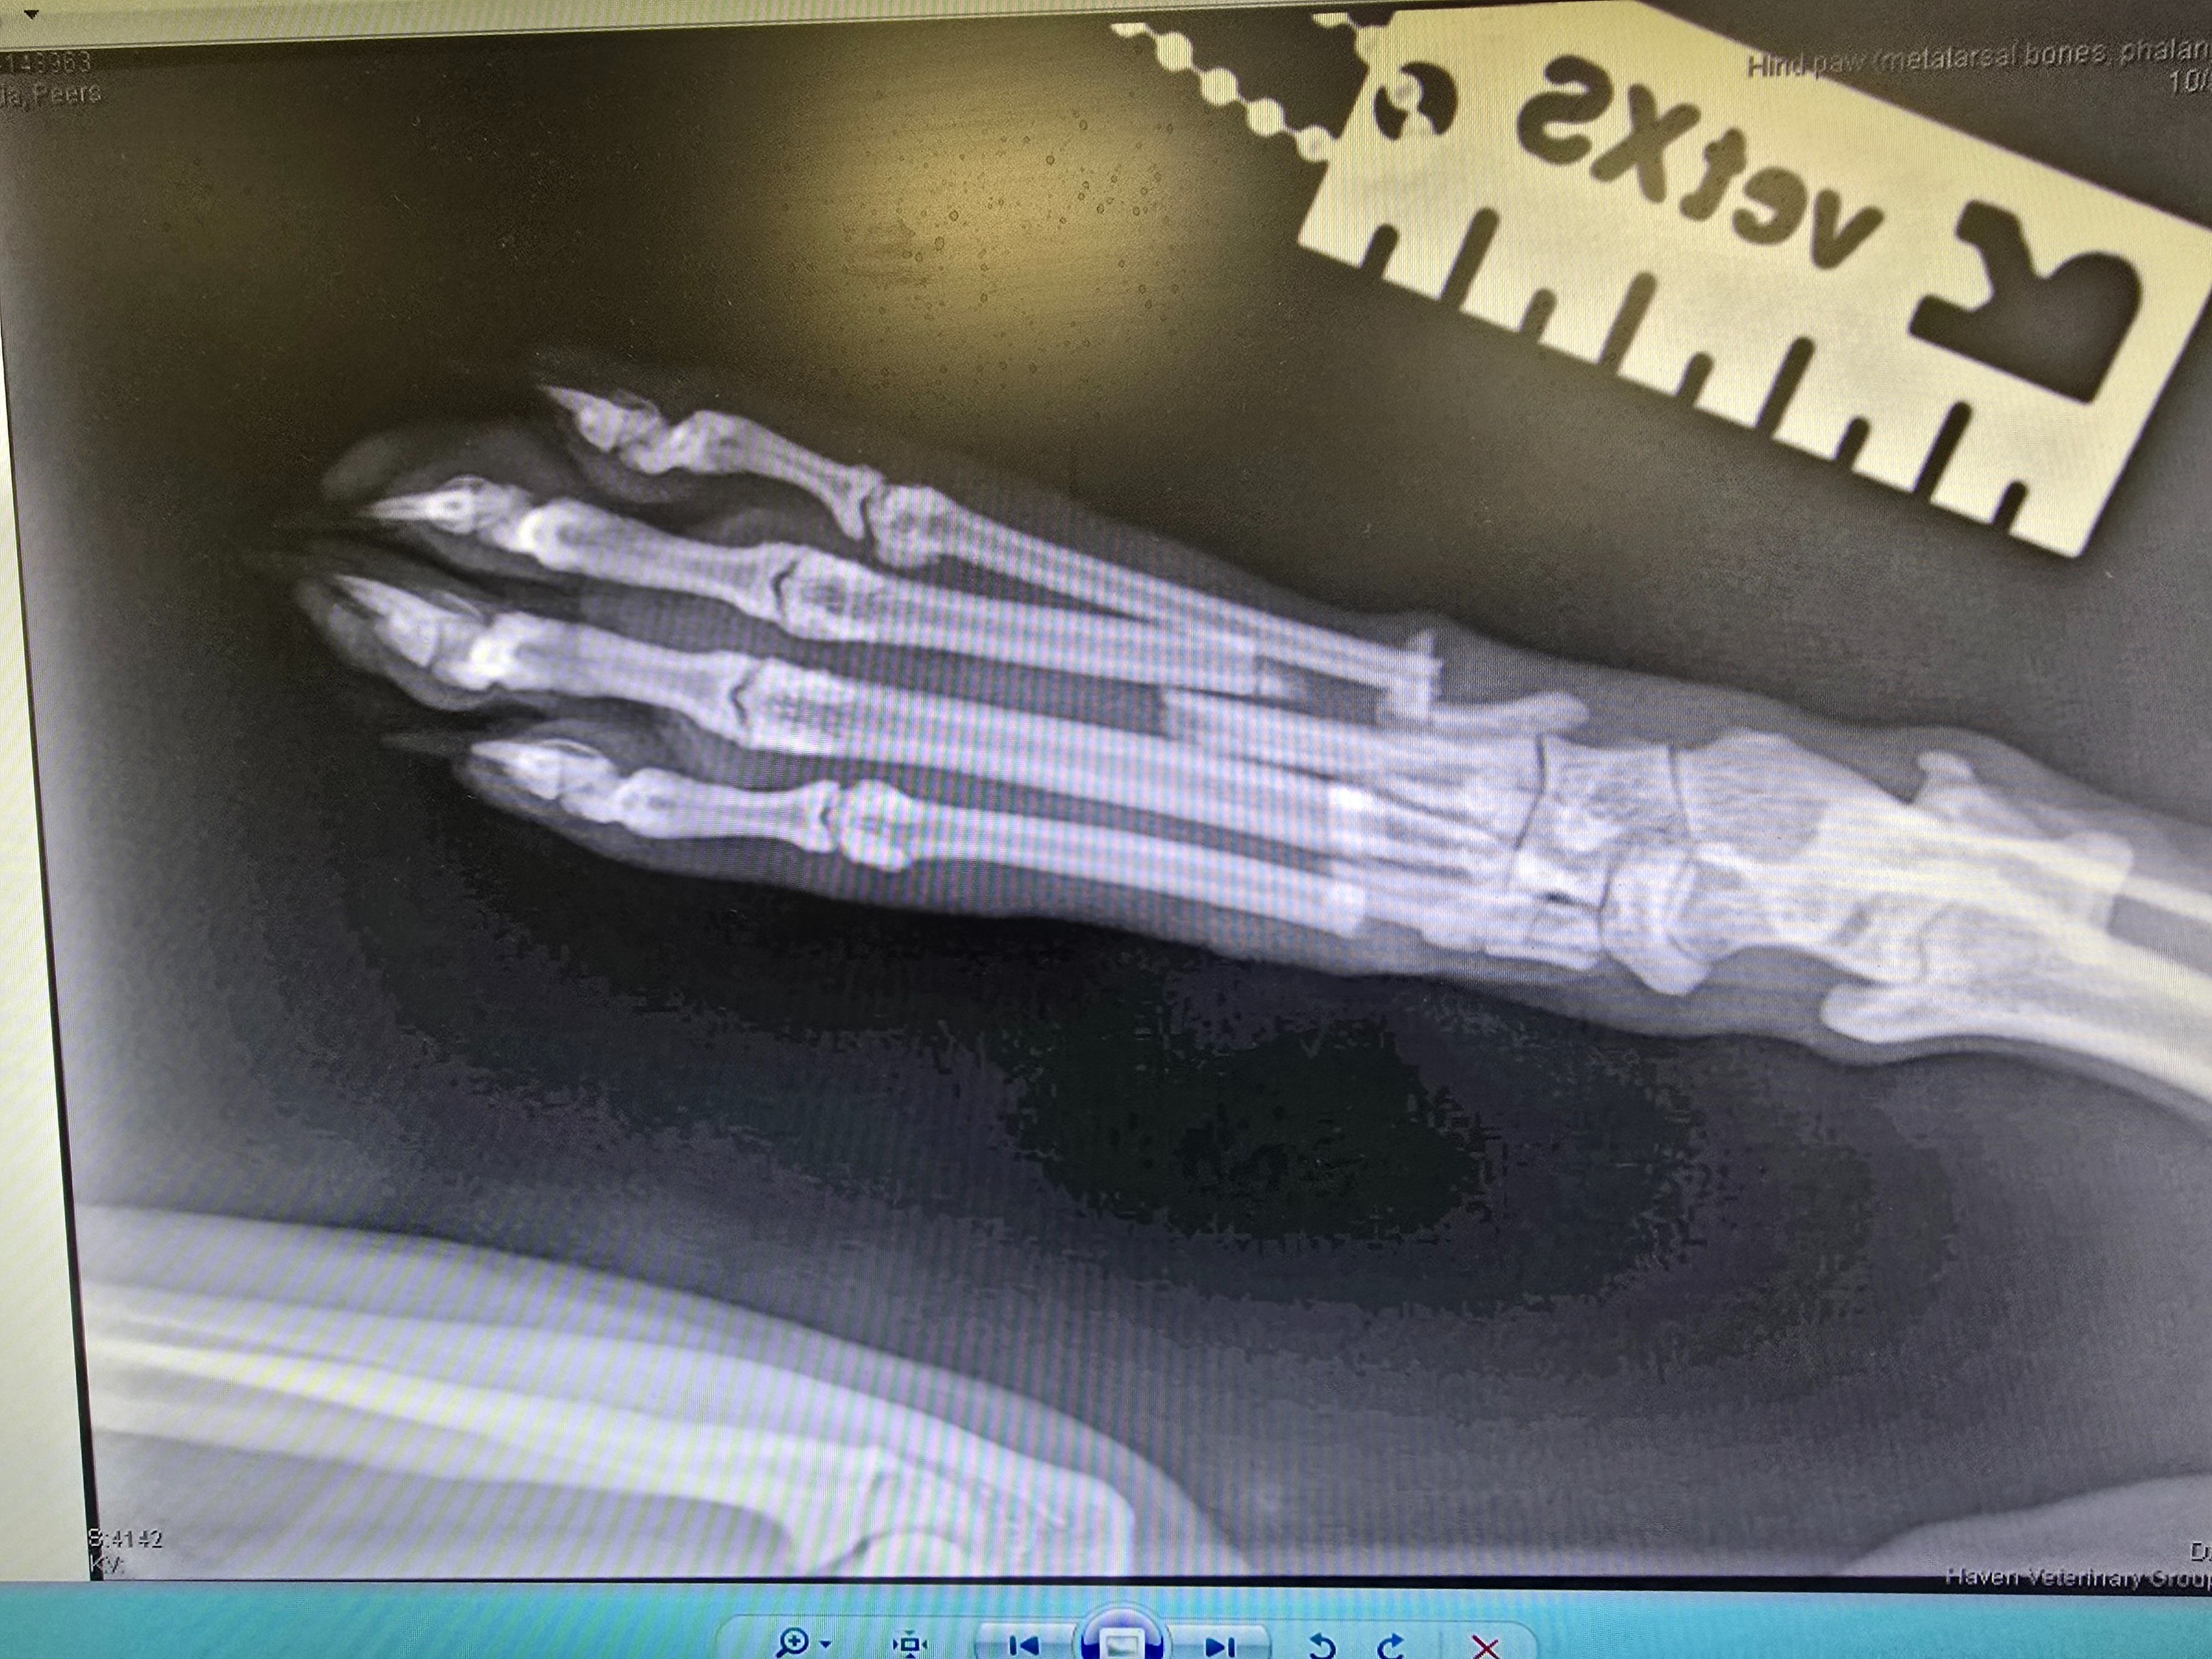

Kai had his surgery to pin his toes and it has failed. We have used all his pet insurance allowance and now he needs another big surgery to put plates and screws in to stabilise his foot. His foot had not healed at all and the pins had moved. Despite us following what they said to the letter. We need your help to raise funds so Kai can have this 2nd surgery. its going to cost £1800 plus £1000 for 2 lots of xrays. Any donations already raised was for the prior surgery and xrays.

Hi my name is Connor and partner Seb. Our cat Kai is 8 and a half years old, and somehow he has managed to break 4 toes on his hind leg. He is covered on pet insurance up to 3k but it very likely will not be enough as he is going to need surgery to repair the breaks by having his bones pinned. That is going to cost a minimum of 3k, possibly more, we are still waiting on hearing from the vets, but then there is more vet visits, more xrays and check ups. If you can please donate to help us help Kai. We would all be very grateful. He is a really loveable cat but also cranky. He will struggle to not be able to go outside but for his own good he will need to be crated for a while to recover. We want to help him recover without worrying about how much it might cost.